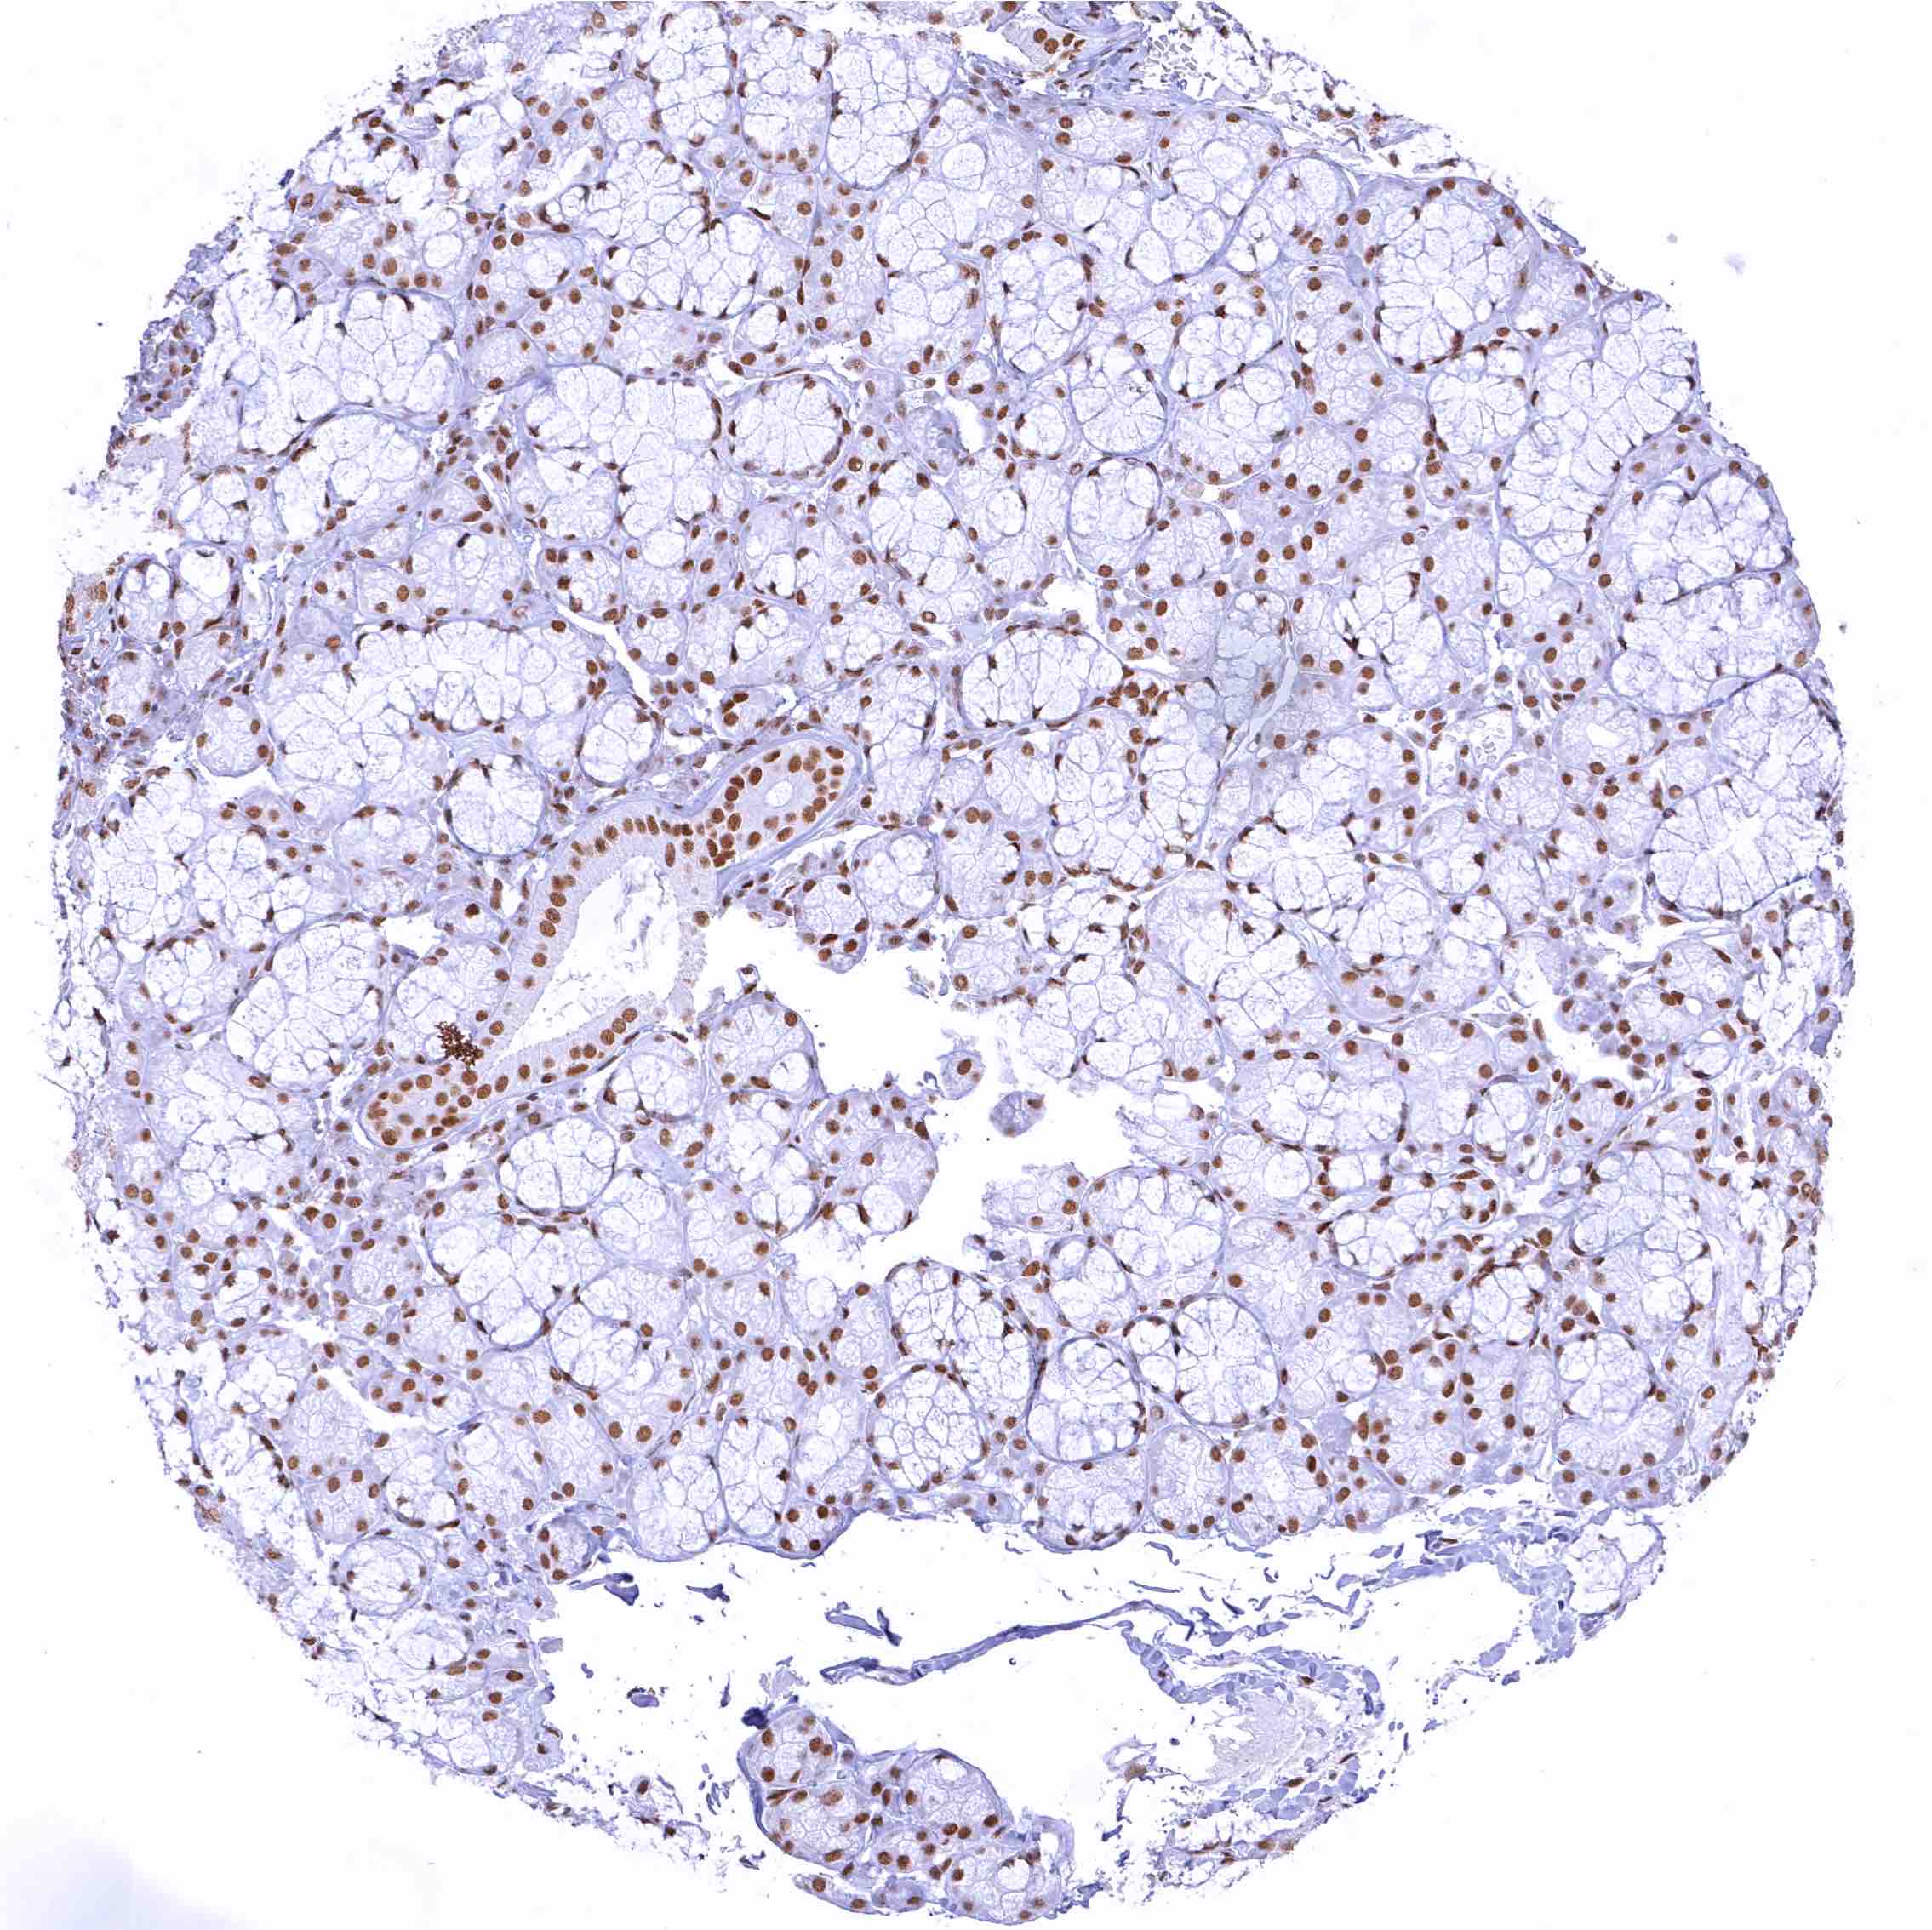

Pancreas